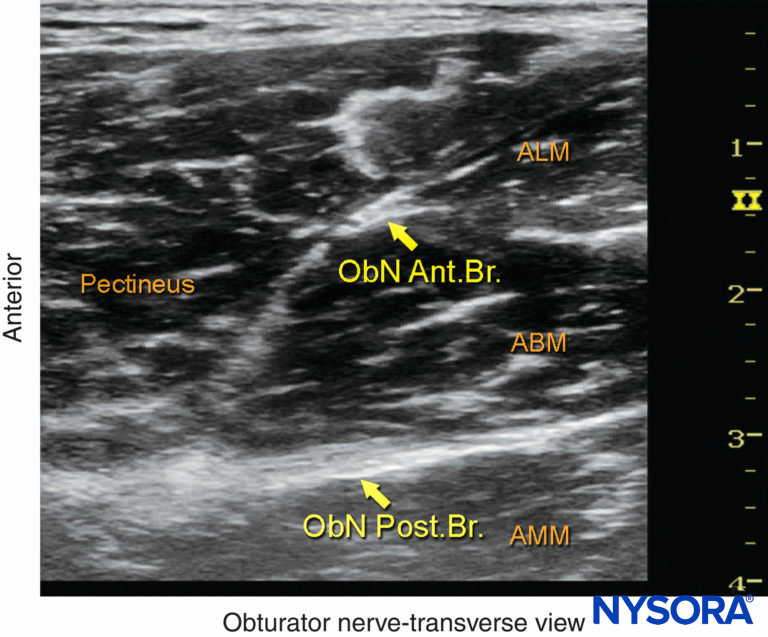

FIGURE 2. Cross-sectional anatomy of relevance to the obturator nerve block. Shown are the femoral vessels (the femoral vein [FV] and femoral artery [FA]), pectineus muscle, adductor longus muscle (ALM), adductor brevis muscle (ABM), and adductor magnus muscle (AMM). The anterior branch of the obturator nerve is seen between the ALM and ABM, whereas the posterior branch is seen between the ABM and AMM.

FIGURE 3. The anterior branch (ant. br.) of the obturator nerve (ObN) is seen between the adductor longus muscle (ALM) and the adductor brevis muscle (ABM), whereas the posterior branch (post. br.) is seen between the ABM and the adductor magnus muscle (AMM).